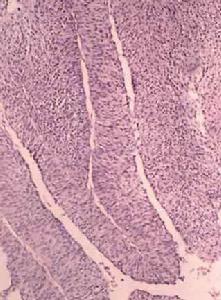

正常膀胱尿路上皮為移行上皮,約3~7層厚。正常上皮細胞表面有大的傘狀細胞覆蓋其下層的一些小細胞,表面的傘狀細胞常為雙核或多核。細胞的大小和形狀隨膀胱的擴張程度而發生變化。在深部黏膜,細胞為圓形、橢圓形、長形或柱狀,包埋在纖維基底膜上,這種結構使細胞之間可以滑動當尿路移行上皮對炎症、慢性刺激或致癌物發生反應時,可發生增生性變化(增生和化生)。90%以上的膀胱癌為移行細胞癌,其生長表現為多樣性,包括乳頭狀,無蒂浸潤,結節狀以及上皮內生長。它具有較大的間變潛能;因此,移行細胞癌可含有梭狀細胞、鱗狀上皮細胞和腺上皮細胞成分。1/3膀胱癌可出現上述成分。移行細胞癌好發於膀胱三角區基底部和側壁但膀胱任何部位均可發生移行細胞癌大約70%膀胱癌為乳頭狀,10%為結節狀,20%為混合型。根據腫瘤細胞分化程度腫瘤分為Ⅰ級Ⅱ級和Ⅲ級Ⅰ級癌指瘤細胞分化良好,移行上皮層次多於7層,細胞呈輕度間變和多形性核胞質比例增大從基底到表層細胞的成熟輕度紊亂,有絲分裂像偶見。Ⅱ級癌的瘤細胞從基底層到表層的成熟高度紊亂,極向喪失,核胞質比例明顯增大伴核多形性,核仁粗大,有絲分裂像較常見。Ⅲ級癌為低分化型核多形性顯著,有絲分裂像多見,瘤細胞與正常移行上皮幾乎無相似之處(圖1)。